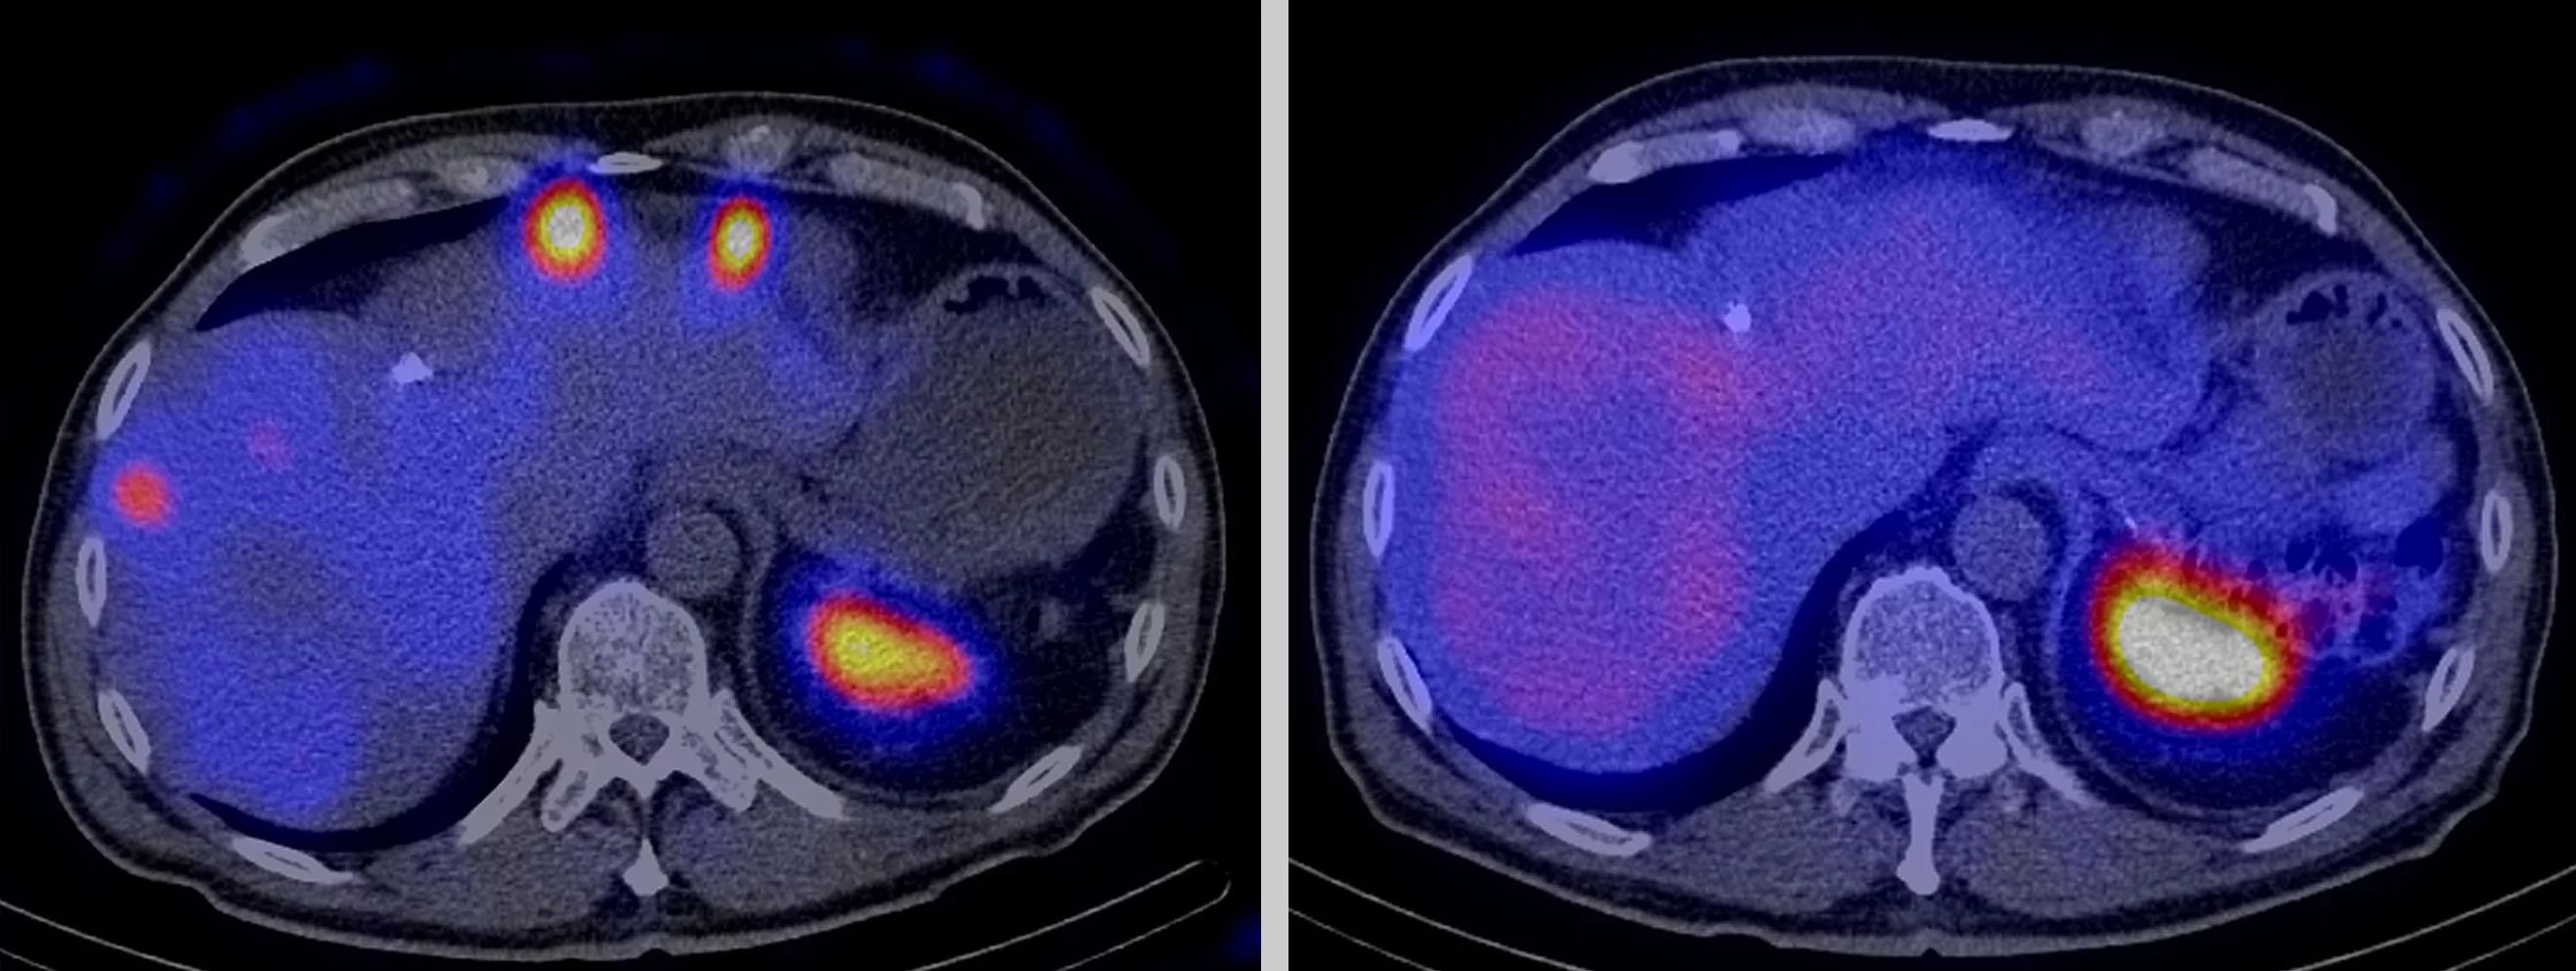

Radioactive drugs also destroy a tumour’s scattered metastases. The two photographs show a cross-section of a patient’s stomach, whose cancer has formed metastases in the liver. The image on the left was taken directly after the first treatment with a radioactive drug. The white, yellow and red circles at the top depict the metastases. The image on the right was taken after the third treatment five months later: no tumour metastases are visible any longer. The large colour circle at the bottom right in the pictures show the spleen, which also stores this radioactive drug heavily in healthy human beings. However, this splenic storage is harmless for the patients during treatment and has no side-effects. The photographs were taken with a SPECT machine, which measures radiation and depicts the distribution of the radioactive drugs in the body. (Photo: University of Basel)